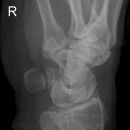

Handgelenk a.p.

Beurteilungskriterien

• Neigung der distalen Radiusgelenkfläche in der Frontalebene: 15 – 35°

• Längenverhältnis Radius – Ulna: Proc.styloideus radii überragt Gelenkfläche der Ulna um 9 –12mm (<9mm Ulna-Plusvariante, >12mm Ulnaminusvariante)

• Kontinuität der drei Karpalbögen:

Proximaler Bogen: proximale Gelenkflächenkonturen von Scaphoid, Lunatum und Triquetum

Mittlerer Bogen: distale Gelenkflächenkonturen von Sacphoid, Lunatum und Triquetum

Distaler Bogen: proximale Gelenkflächenkonturen von Capitatum und Hamatum

Fehlende Abgrenzbarkeit, Versatz oder Unterbrechung sind als pathologisch zu bewerten und deuten auf eine Luxation hin.

Trapezförmige Darstellung des Lunatum in Neutralstellung? Augenzeichen des Hamulus? Superposition von Pisiforme und Triquetum? Metacarpale III in Projektion innerhalb der Radiusgelenkfläche? Lunatum zu >50% über Radiusgelenkfläche? Cave: bei Radial- oder Ulnarduktion wandert das Lunatum in umgekehrter Richtung.

• M-förmiger Verlauf der Gelenkspalten der Carpometacarpalgelenke? Luxationsstellung in den Carpometacarpalgelenken (meist dorsale Luxation)?

• Gelenkspaltweiten des Radiocarpalgelenk 2 – 2,5mm, der Carpometacarpalgelenke 1 –2mm, distales Radioulnargelenk 2mm, Gelenksspaltweiten der Intercarpalgelenke 1,5 – 2mm

Cave: SL-Dissoziation (Ruptur des SL- Bandes, häufigste Gefügestörung): Terry-Thomas-Sign = SL-Spalt > 3mm, Siegelringzeichen = Ringförmige Transparenzminderung im mittleren Scaphoiddrittel durch orthograde Projektion der Taille infolge Rotation.

• Obliteration des Scaphoidfettstreifens?

• Täuschungsmöglichkeiten durch Vielzahl akzessorischer Ossikel (abgerundete, zirkulkär-geschlossene Kortikalis), geteilte Handwurzelknochen (Scaphoid, Lunatum, Pisiforme) und Gefäßkanälchen

• Target areas leicht zu übersehender Frakturen: distales Radioulnargelenk, Processus styloideus radii et ulnae, Basen der Metacarpalia (v.a. MCP I), Hamulus.

• Grundsätzlich gilt: unklare Verhältnisse ->CT-Indikation